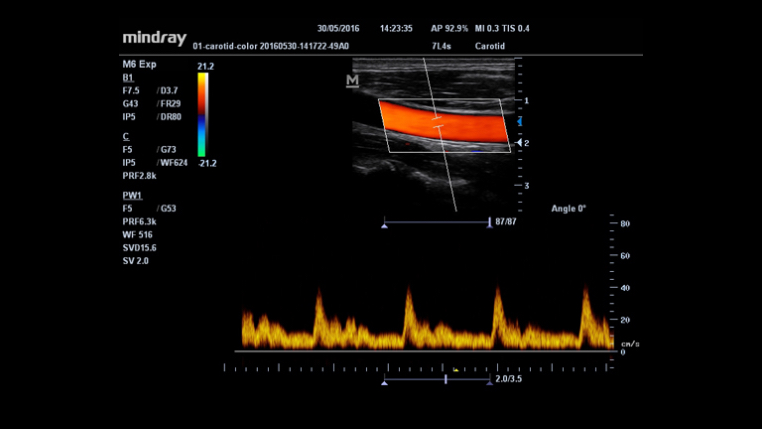

IMT (Grosor ?ntima-Media)

Automedición de grosor de pared anterior y posterior proporcionando un estado preciso de la carótida.

Funci√≥n √Їnica de Mindray: Una funci√≥n √Їnica de Mindray: realice un seguimiento continuo del flujo de color y optimice la mejor posici√≥n del cuadro de color y el mejor √°ngulo en la adquisici√≥n de im√°genes en tiempo real.